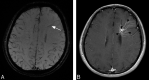

A developmental venous anomaly presenting atypical findings on susceptibility-weighted imaging